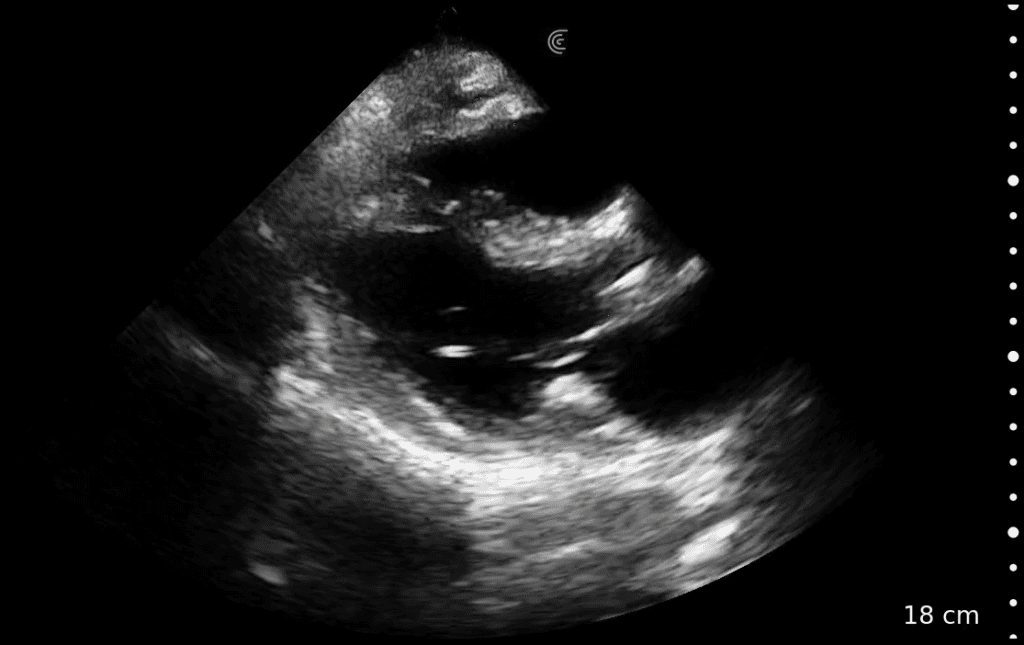

• Perform goal-directed echocardiography at the bedside

• Monitor patient changes during cardiac arrest

Cardiac

Quick Cardiac

Comprehensive package for precise cardiac function assessment.